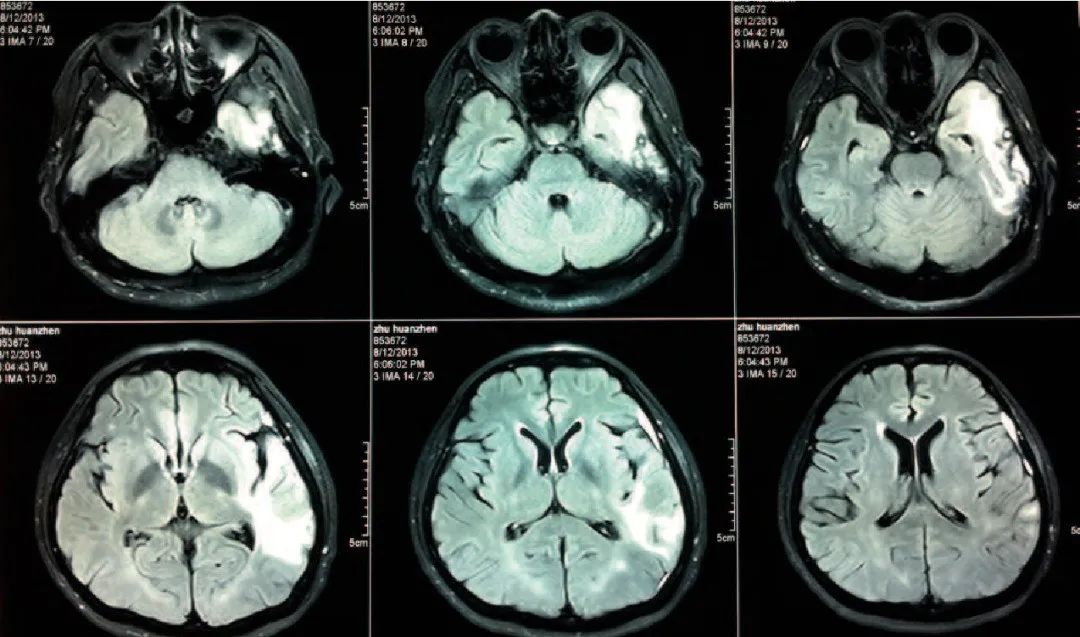

在很多外国口音综合征案例中,共同之处是大脑左半球的特定区域有损伤,而普通人的语言功能区就位于左半球。当然,脑损伤都是很随机的,在被报告的外国口音综合征中,有三分之二的患者还有其他的语言缺陷症状,比如失语症,阿斯特丽德的案例正是如此。